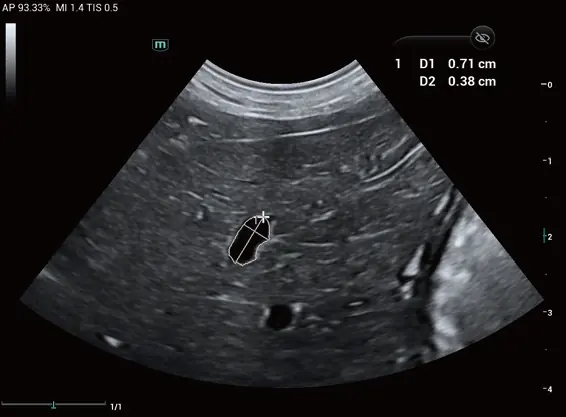

Lezyon sınırlarını otomatik olarak tanımlayan ve çoklu hassas ölçümler gerçekleştiren otomatik izleme, ölçüm ve hesaplama aracıdır. Bu teknoloji, kullanıcı müdahalesini en aza indirirken ölçüm doğruluğunu maksimize eder.